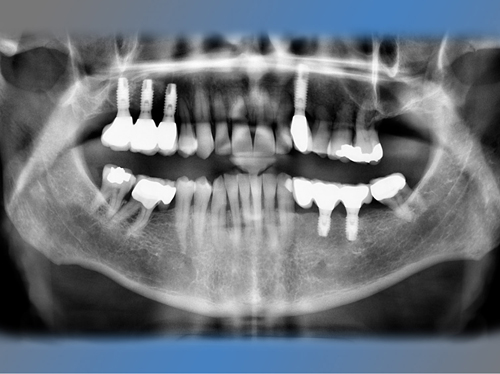

Félix Miquel Sempere acude en 2001 a la clínica dental IDIM tras varios intentos fallidos de colocación de implantes dentales en otra clínica dental.

En el maxilar superior tenía poco hueso debido a la presencia del seno maxilar, por lo que se le trato con la técnica de injerto óseo conocida como elevación de seno directa para poder colocarle implantes.

También se le sustituya el puente de la mandíbula que presentaba movilidad debido a caries en los dientes pilares por dos implantes y se le coloca otro implante en un canino superior ausente.